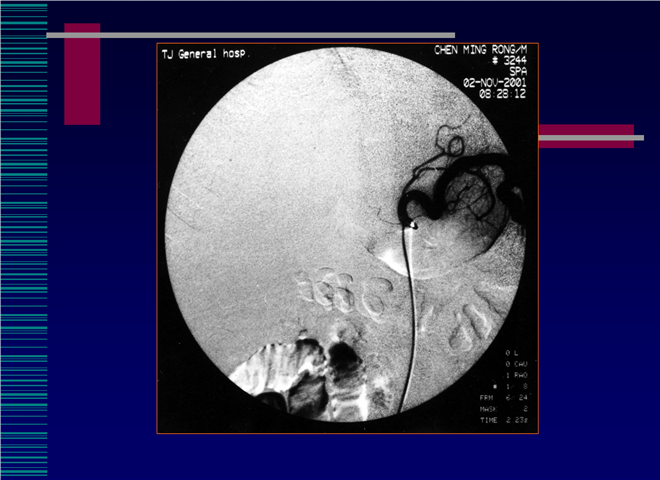

05_肝癌介入治疗